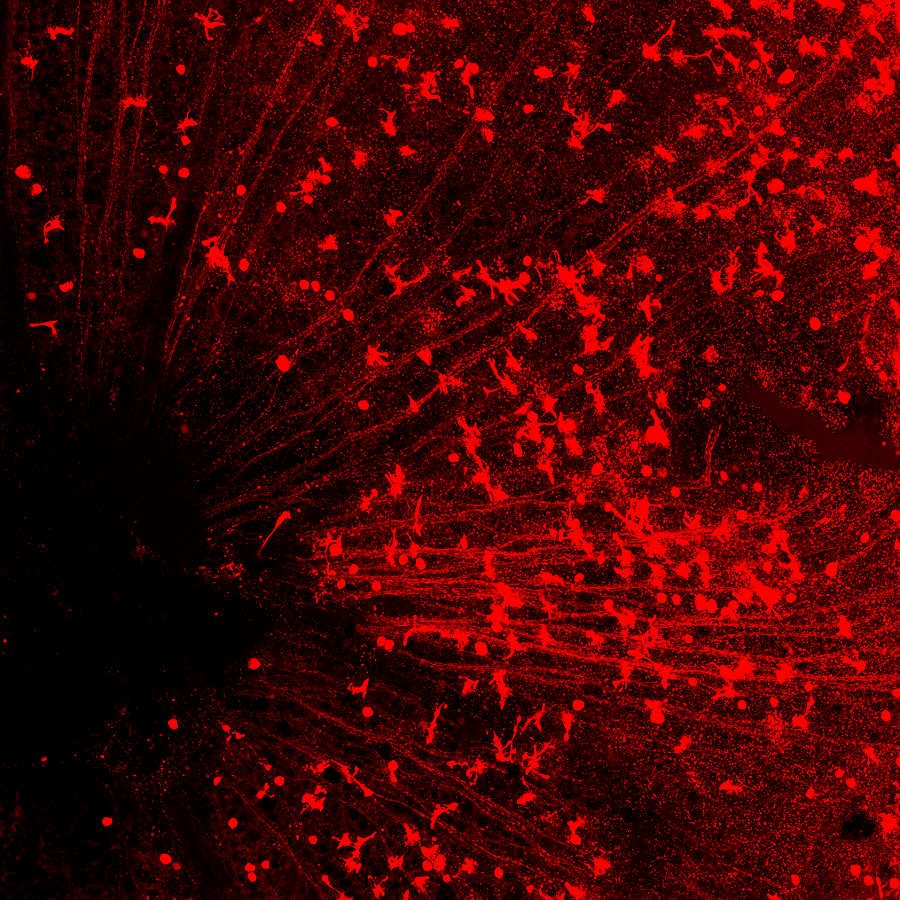

圖注:(上)CasRx通過靶向的降解Ptbp1 mRNA從而實現(xiàn)Ptbp1基因表達的下調(diào)。(中)視網(wǎng)膜下注射AAV-GFAP-CasRx-Ptbp1可以特異性的將視網(wǎng)膜穆勒膠質(zhì)細胞轉(zhuǎn)分化為視神經(jīng)節(jié)細胞,轉(zhuǎn)分化而來視神經(jīng)節(jié)細胞可以和正確的腦區(qū)建立功能性的聯(lián)系,并且提高永久性視力損傷模型小鼠的視力。(下)在紋狀體中注射AAV-GFAP-CasRx-Ptbp1可以特異性的將星形膠質(zhì)細胞轉(zhuǎn)分化為多巴胺神經(jīng)元,從而基本消除了帕金森疾病模型小鼠的運動癥狀。

在小鼠的視網(wǎng)膜上,紅色圓形的細胞是再生出的視神經(jīng)節(jié)細胞,可以看到一條一條的紅線匯集到眼睛中間的視盤(左下黑洞區(qū)域),這是再生出的視神經(jīng)節(jié)細胞發(fā)出的軸突,它們將通過視盤傳到視神經(jīng),然后再到大腦。

視神經(jīng)部位是連接眼睛和大腦的橋梁。每一條紅色的線是每一個再生出來的視神經(jīng)節(jié)細胞發(fā)出的軸突,通過這里,這些新生軸突將會與大腦中處理視覺信號的區(qū)域正確相連。